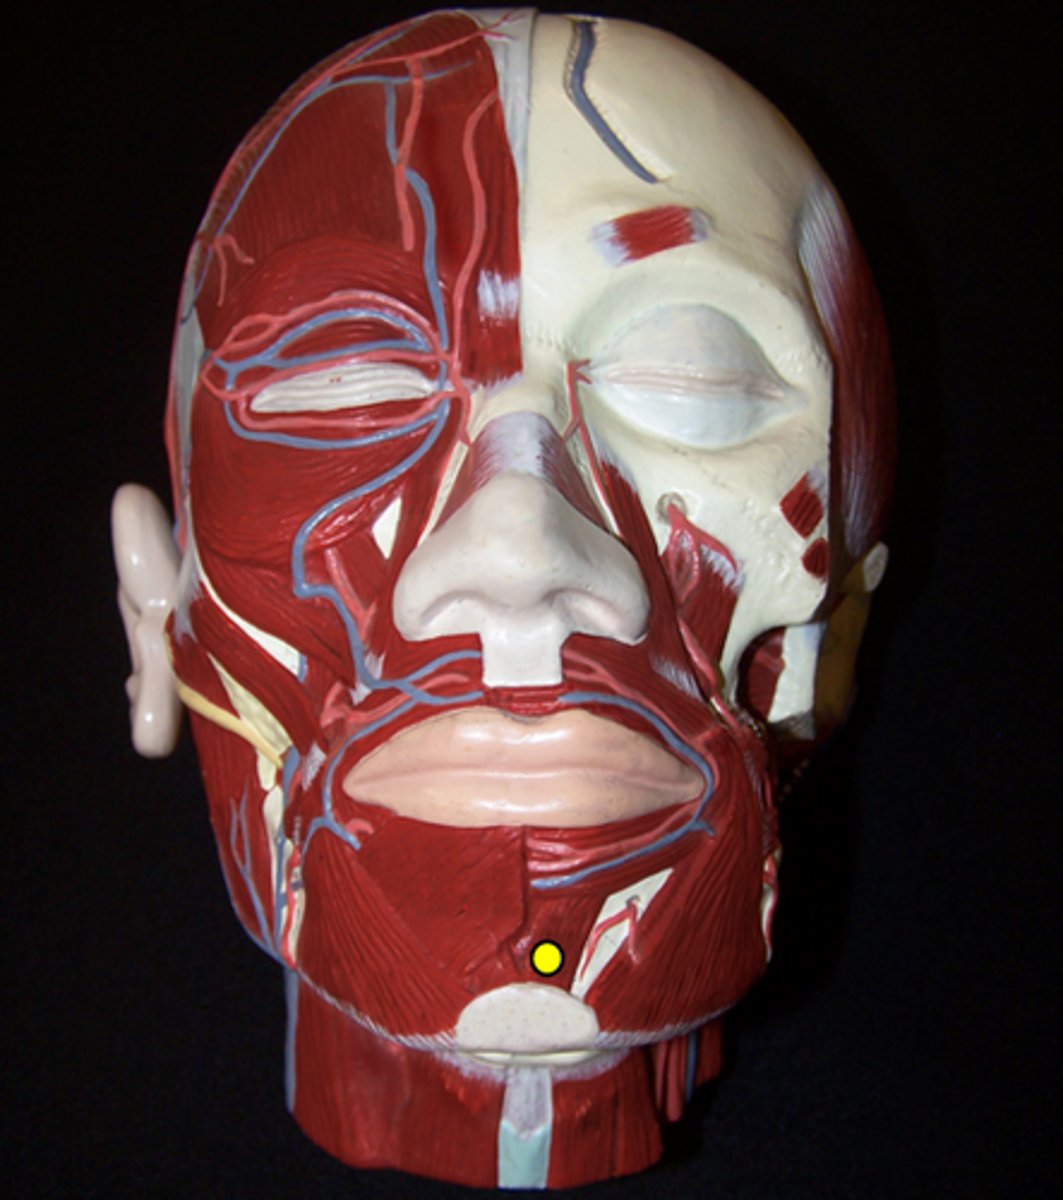

Mentalis